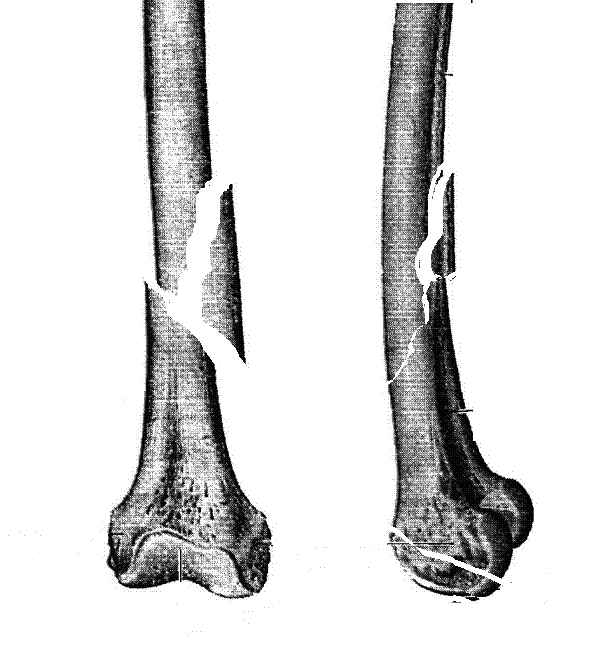

Женщина 66 лет 15.10.2006 получила закрытый окольчатый перелом правой бедренной кости в с\з-н\з со смещением отломков. 17.10.2006 доставлена в травм.отделение (2-е суток лежала одна дома). При поступлении наложено скелетное вытяжение за бугристость большеберцовой кости - груз 5 кг, затем увеличен до 7 кг. Схематические рисунки контрольных Р-грамм прилагаются (прошу прощения за отсутствие Р-грамм, постараюсь "донести").В связи с отсутствием материальных средств и "удовлетворительным" положением отломков решено было скелетное вытяжение оставить как окончательный метод лечения. На 20.11.2006 отека правого бедра нет, пальпаторно умеренная болезненность в месте перелома, крепитации отломков нет (и по-видимому не было изначально),подвижность в месте перелома сохранена, но не выражена. Двигательных, чувствительных и трофических расстройств правой нижней конености нет. Уважаемые коллеги! Какова дальнейшая тактика в случае вероятной интерпозиции тканей? Больная "кровавое" оперативное лечение не "потянет" материально. Даст ли в данном случае что-то АВФ закрыто?

Нету там интрепозиции. Если картинка рентгенологическая близка к тому, что Вы прислали на рисунке.

Представляю вашему вниманию снимки в динамике